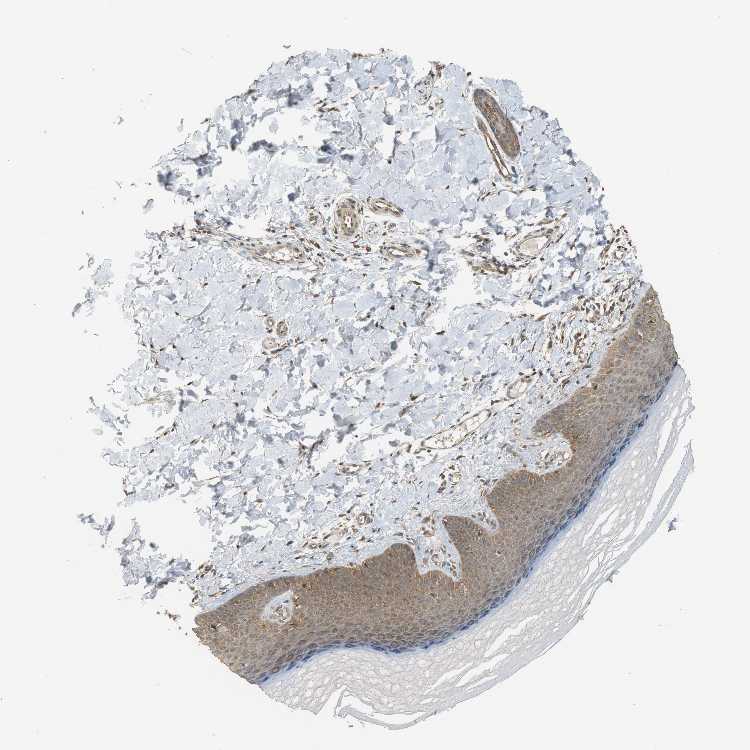

SKIN 2 - Antibody stainingi

Antibody staining in the annotated cell types in the current human tissue is reported as not detected, low, medium, or high, based on conventional immunohistochemistry profiling in selected tissues. This score is based on the combination of the staining intensity and fraction of stained cells.

Each image is clickable and will lead to virtual microscopy that enables deeper exploration of all samples and also displays staining intensity scores, fraction scores and subcellular localization as well as patient and tissue information for each sample.

Antibody HPA006431Antibody CAB013481

Cells in basal layer Low-

Cells in corneal layer Not detected-

Cells in granular layer Not detected-

Cells in spinous layer Low-

Endothelial cells Low-

Epidermal cells -Medium

Extracellular matrix Not detected-

Fibrohistiocytic cells Medium-

Langerhans cells Low-

Lymphocytes Medium-

Melanocytes Medium-

Vascular mural cells Low-